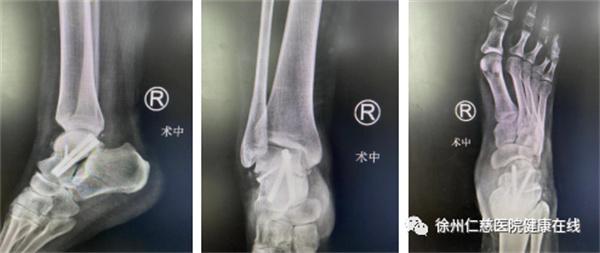

术前X线片,距骨骨折伴脱位

在踝关节镜下探查,将骨折脱位复位,骨科机器人三维扫描,电脑软件模拟规划置钉,精准固定骨折。

术后X线,距骨骨折复位,螺钉精确固定